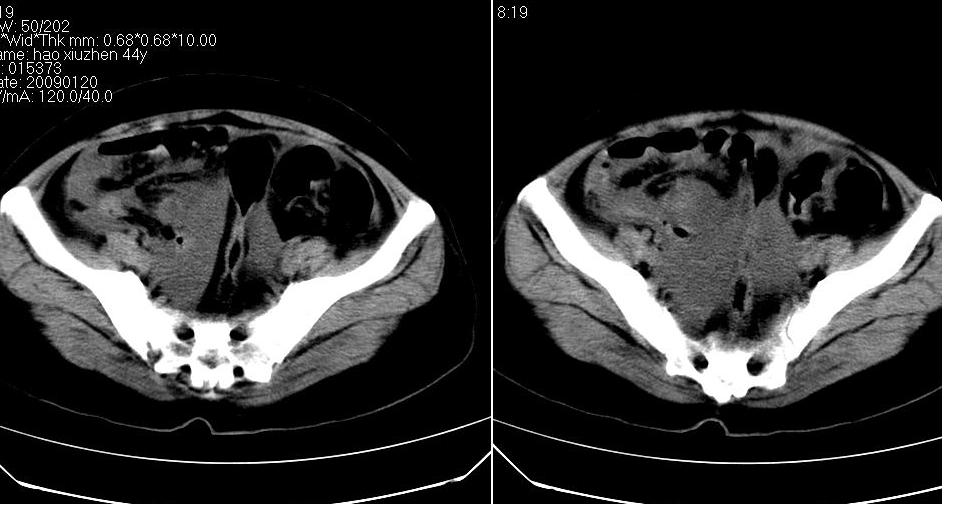

标题: CT17773B盆腔CT平扫

女 44岁,于ct17773号病例同一个病人。有结果我会尽快告诉大家。

盆腔及腹腔积液,原因待查。